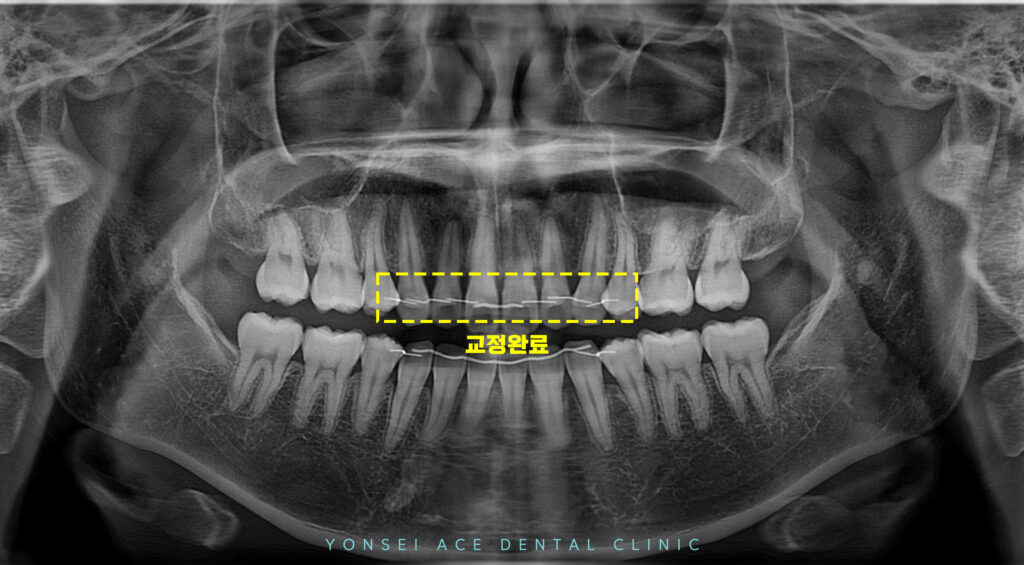

현재는 교정 치료가

완료된 상태였습니다.

교정을 진행하면서 브라켓이 붙어 있었을 때는

장치에 가려져 잘 인지하지 못했던 부분이

브라켓이 제거되면서 선명하게 드러났습니다.